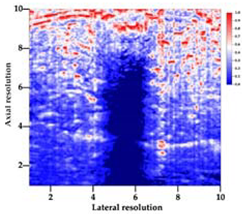

3.5. Echogenicity

| Aerogel Type | US Image | Normalized Intensity Map | 3D Intensity Map | |

| 1 | Muscle |  |  |  |

| 2 | X-silica |  |  |  |

| 3 | X-silica-La2O2S:Eu |  |  |  |

| 4 | SMPU-Mix-14 |  |  |  |

| 5 | SMPU-Mix-18 |  |  |  |

| 6 | BRF-CA |  |  |  |

| 7 | ARF-CA |  |  |  |

| 8 | X-Ca-Alg-2 |  |  |  |

| 9 | X-Ca-Alg-1 |  |  |  |

| Aerogel Type | Imaging Frequency (MHz) | Optimal Frequency (MHz) | Echogenicity | Image Characteristics | Impedance Mismatch (%) | |

| X-silica | 6.5–13.4 | 13.4 MHz | Hypoechoic | Least Hyperechoic | Distinct linear boundary | 92.03 |

| X-silica-La2O2S:Eu | 6.5–13.4 | 13.4 MHz | Hypoechoic | Least Hyperechoic | Distinct linear boundary | 90.28 |

| SMPU-Mix-14 | 6.5–13.4 | 11 MHz | Hyperechoic | Moderately Hyperechoic | Irregular boundary | 98.33 |

| SMPU-Mix-18 | 6.5–13.4 | 11 MHz | Hyperechoic | Moderately Hyperechoic | Irregular boundary | 98.23 |

| BRF-CA | 6.5–13.4 | 13.4 MHz | Hyperechoic | Hyperechoic | Waterfall appearance | 97.16 |

| ARF-CA | 6.5–13.4 | 13.4 MHz | Hyperechoic | Hyperechoic | Waterfall appearance | 97.12 |

| X-Ca-Alg-2 | 6.5–13.4 | 11 MHz | Isoechoic | Strongly Hyperechoic | Irregular boundary | 98.03 |

| X-Ca-Alg-1 | 6.5–13.4 | 11 MHz | Isoechoic | Strongly Hyperechoic | Irregular boundary | 97.97 |